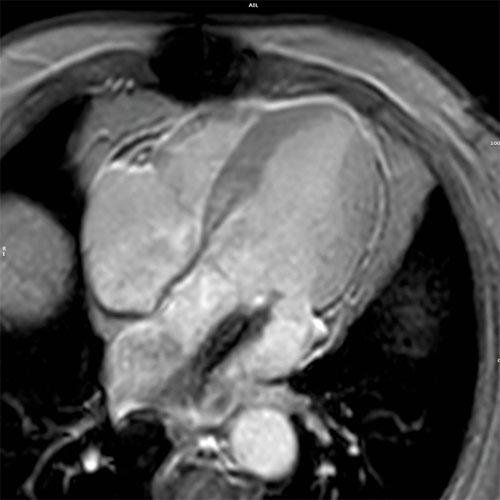

Cardiac MR images of a patient with non-ischemic cardiomyopathy showing delayed enhancement and severe mitral regurgitation.

EPI cine - 4 chamber view